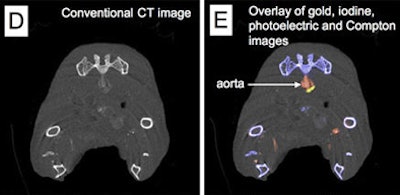

In a 2010 study of a gold high-density lipoprotein nanoparticle targeted at atherosclerosis, Cormode and colleagues showed that nanoparticles can distinguish several different components in a single scan. The group performed spectral imaging on a preclinical CT scanner developed by Philips Healthcare to differentiate gold (Au-HDL), iodine-based contrast, and calcium phosphate in phantoms. The gold nanoparticles were injected in mice and followed 24 hours later by an iodine-based contrast agent.

The gold particles were detected in the aortas of the mice, while the iodine-based contrast agent was highlighted in the blood and the calcium-rich tissue of the skeleton during a single CT scan. Microscopy showed that the gold was primarily localized in macrophages in the aorta, thereby showing that spectral CT also provided information about the macrophage burden (Radiology, September 2010, Vol. 256:3 pp. 784-782).

| Above, schematic illustration of macrophage-targeted gold core nanoparticle Au-HDL. HDL = high-density lipoprotein. Below, conventional CT image near bifurcation of aorta in mouse (left) contrasts with spectral CT images (right) following injection with Au-HDL and an iodinated emulsion contrast agent (Fenestra VC). Images republished with permission of Radiology, September 2010, Vol. 256:3, pp. 784-782). |